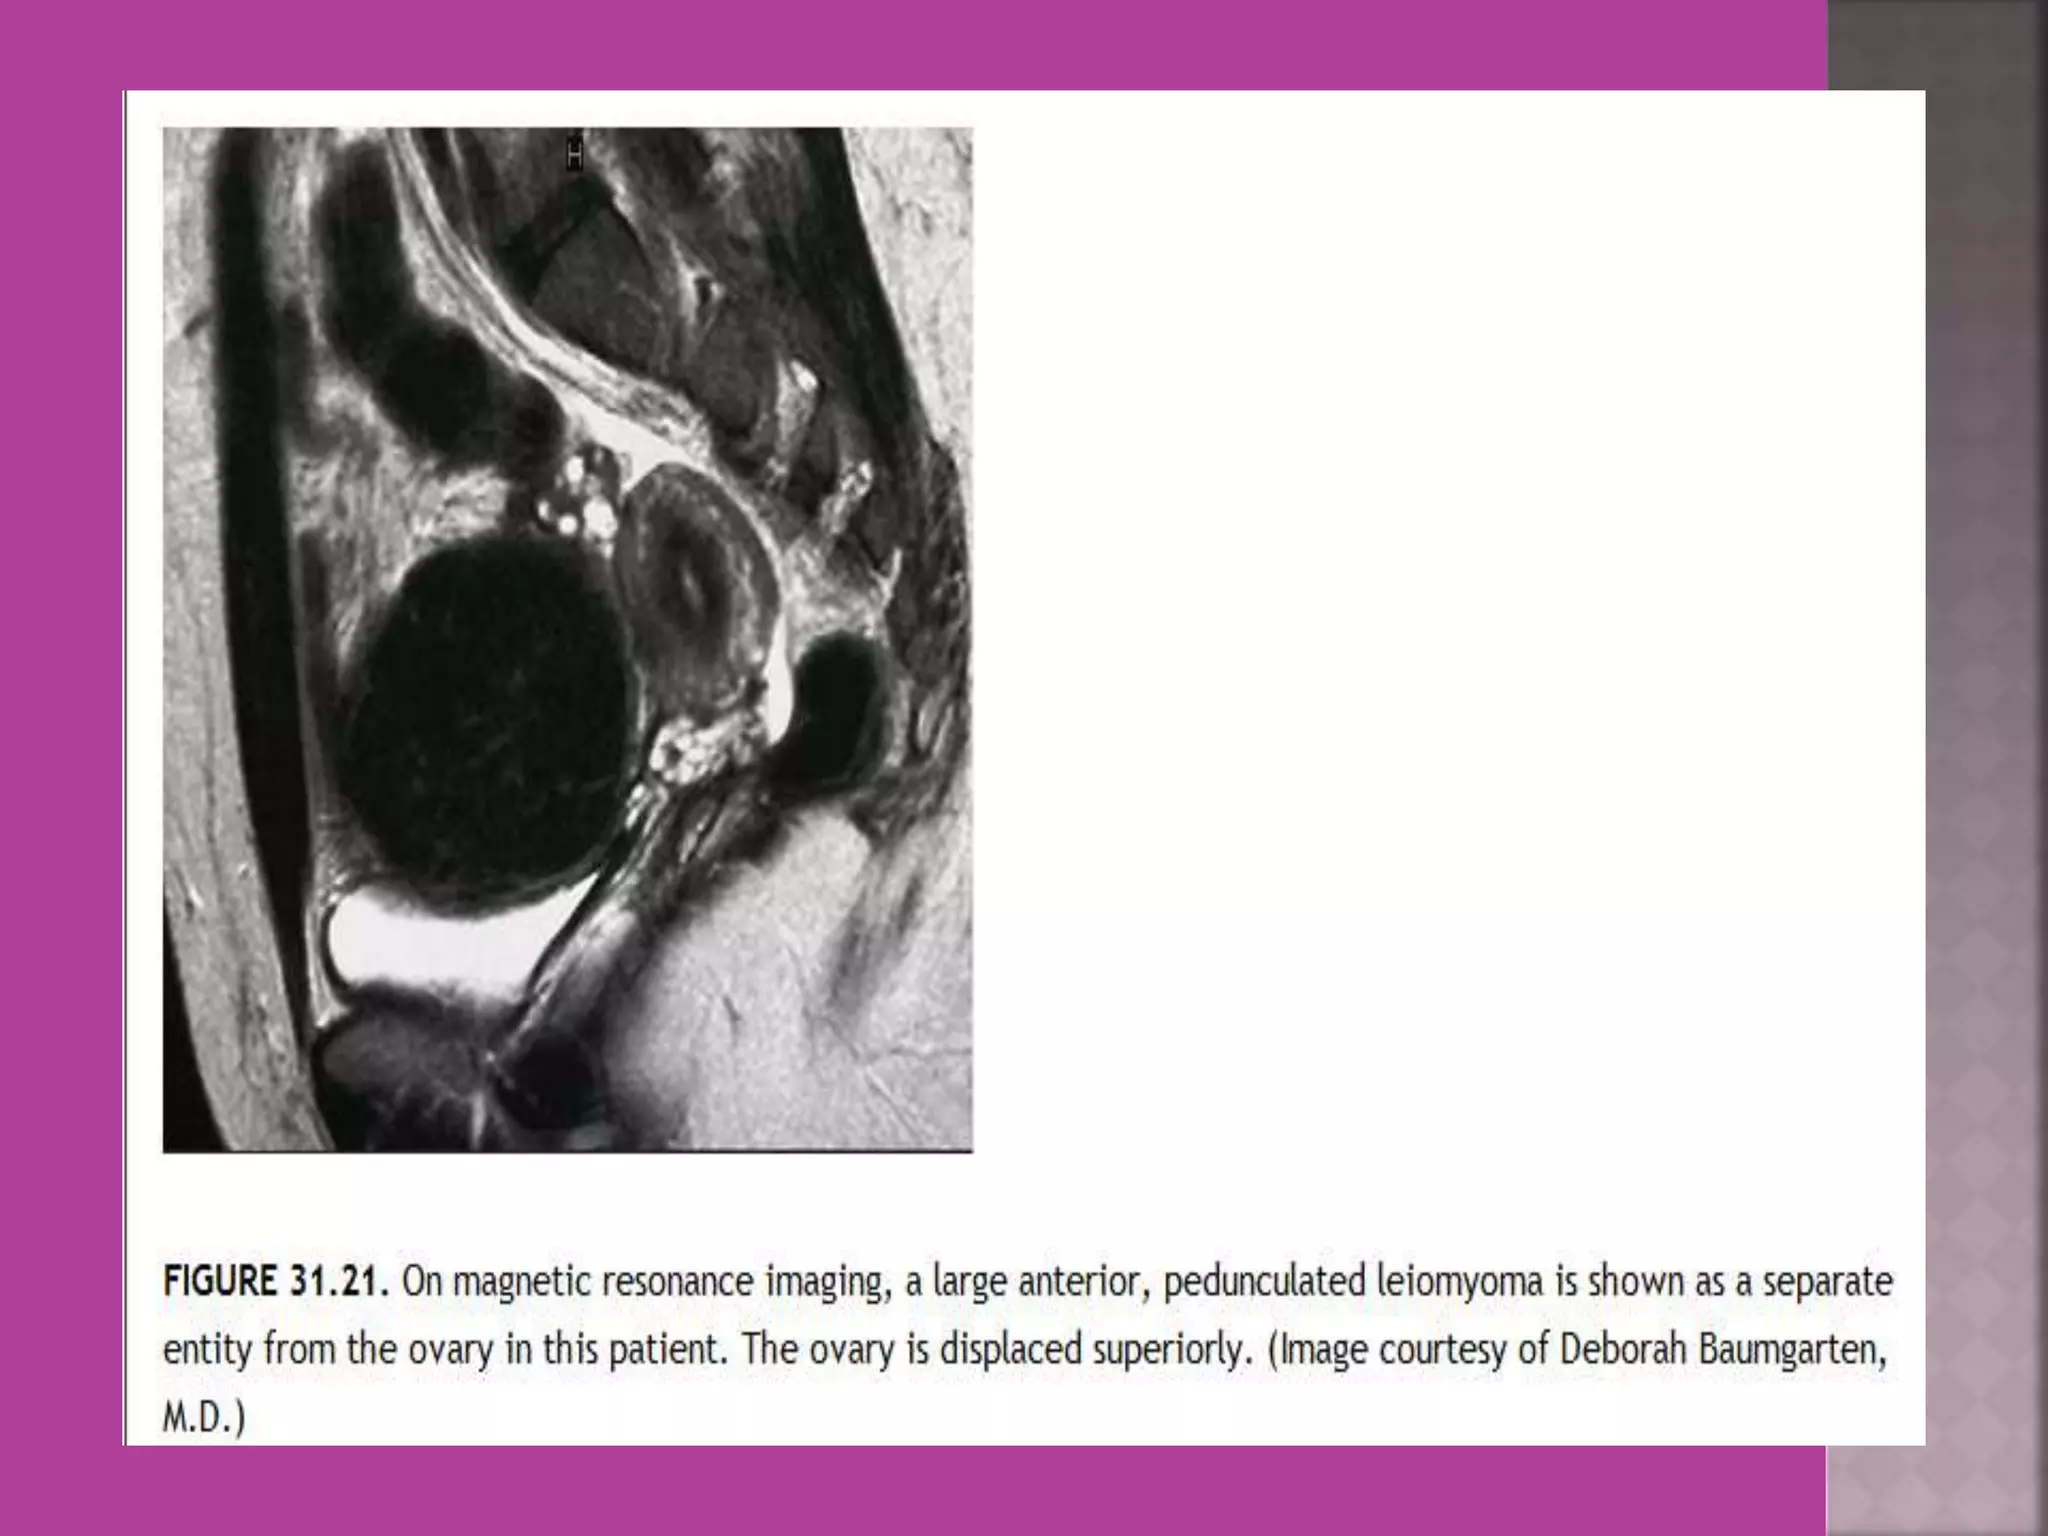

 Myoma—to differentiate myoma from

adenomyoma.localization of myoma—sub

serous/ intra mural or sub mucous.

 Study ofnormal uterus and adnexa – with aim to have clear image of normal myometrium, endometrium , ovary and follicles within the ovary.  Myoma—to differentiate myoma from adenomyoma.localization of myoma—sub serous/ intra mural or sub mucous.  Adenomyosis---accurate diagnosis.  Congenital uterovaginal anomalies— bicornuate, septate,subseptate , unicornuate, didelphys ,rudimentary horn and vaginal atrasia etc